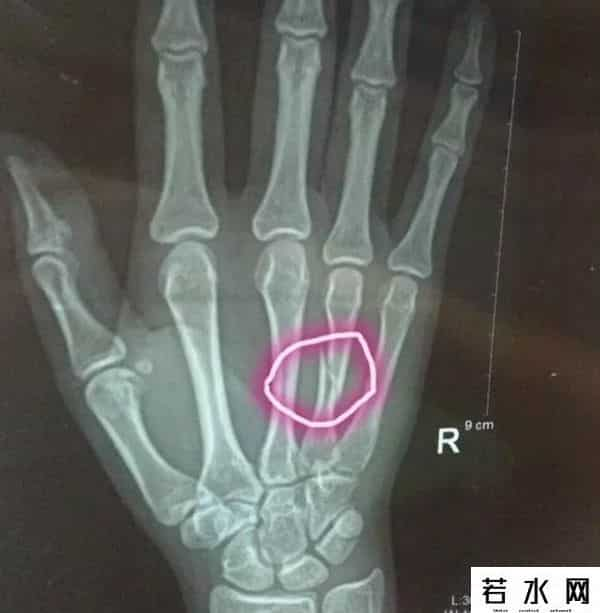

别以为女骑士就是剽悍的女汉子,楚戈可是个文艺范女青年。钢琴、高尔夫,偶尔看看书,满满的小资风情有没有。对了,女神可是川崎粉,有多少人和女神一样呢?骑车出门,安全第一,要时刻注意安全,不然受伤就不好了,看咱们的楚戈女神身上的伤,

触目惊心啊,大家心疼么?